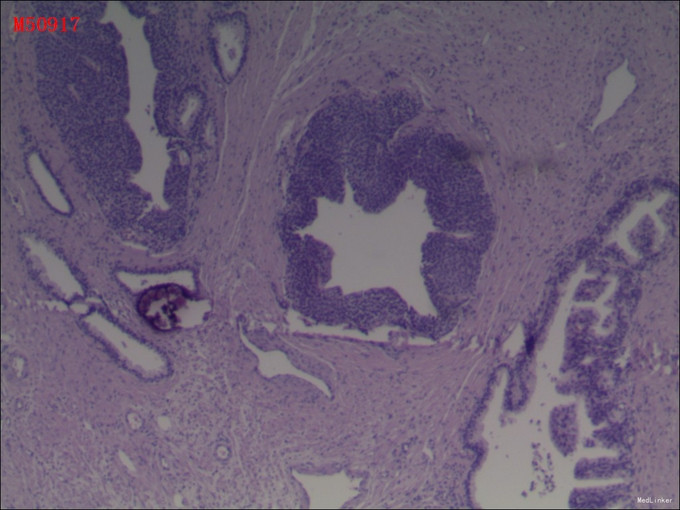

病理:1(前列腺及精囊腺)送检5x4x4cm前列腺一个,左侧精囊腺4x2x0.5cm,输精管长5cm,右侧同左侧。镜下:前列腺腺癌,Gleason评分3+3=6分。双侧输精管及精囊腺未见癌。2(膀胱颈切缘组织)送检直径0.5cm组织一块,全埋制片。镜下:膀胱壁组织,未见癌。3(右侧部分精囊腺)送检直径1cm组织一块,切开全埋制片。镜下:右侧精囊腺组织,未见癌。